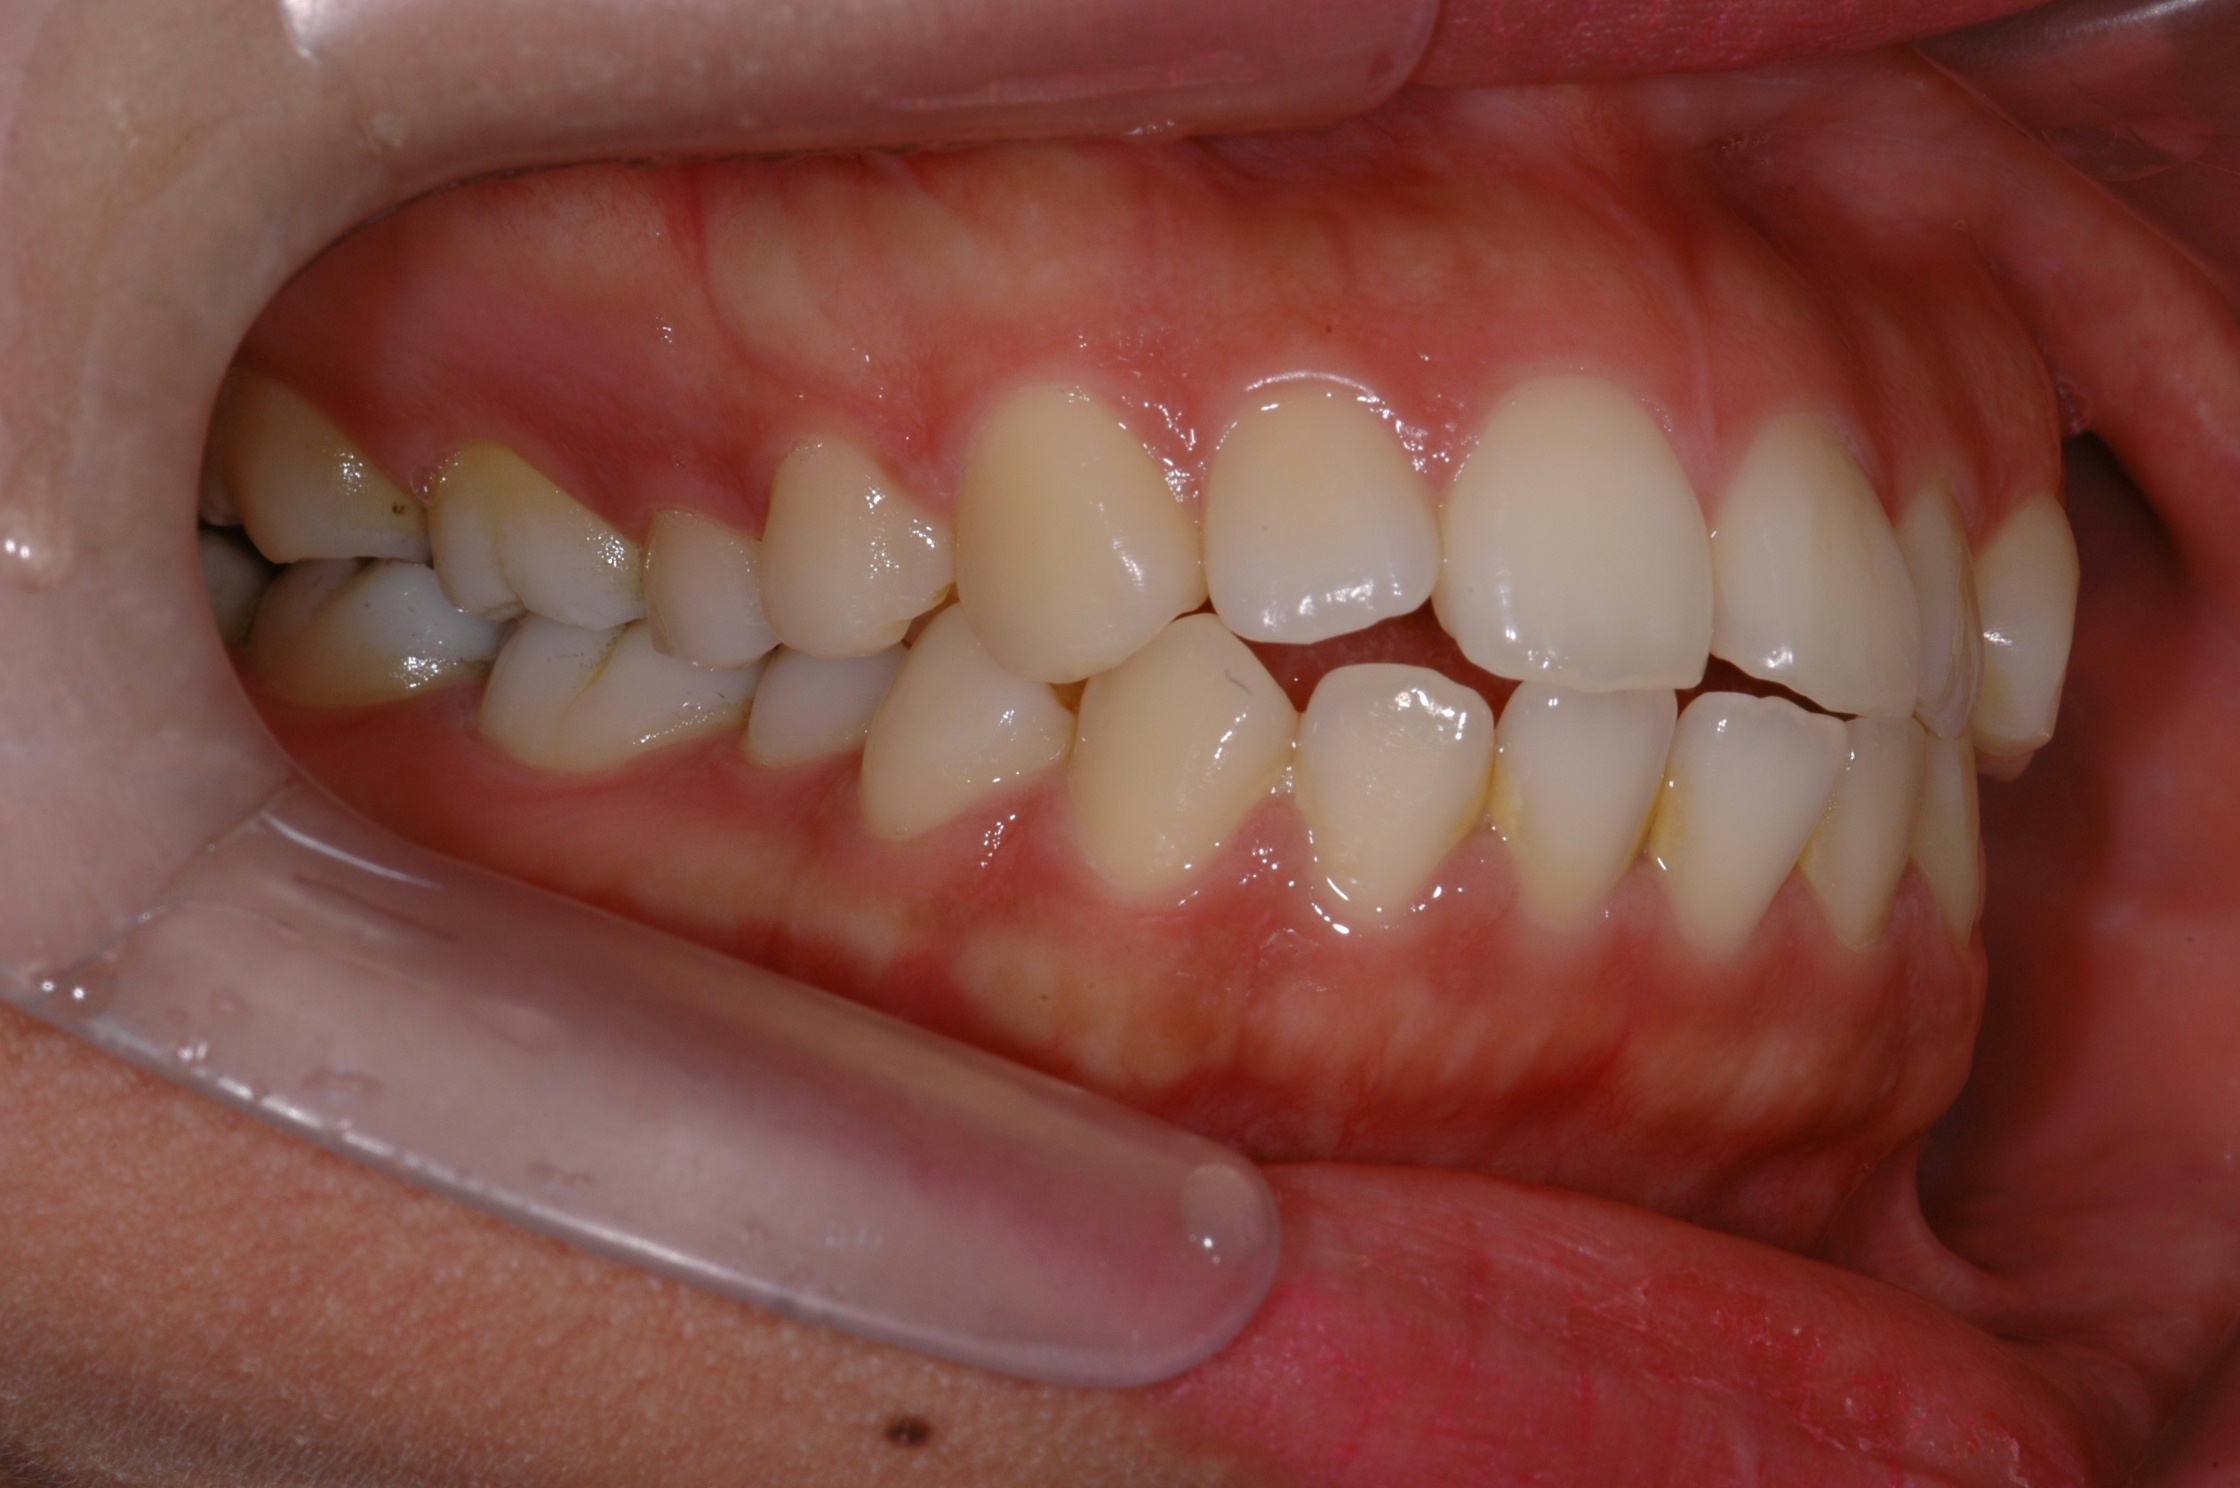

치료 전 사진입니다.